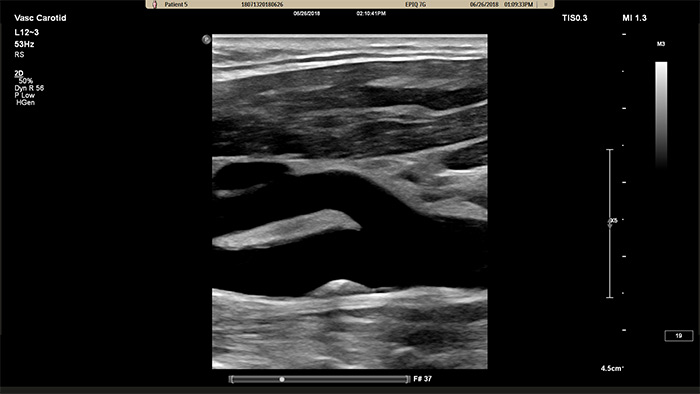

Der neue XL14-3 xMATRIX Schallkopf hat beeindruckende 56.000 Elemente, die alle mit einem separaten Mikrokanal verbunden sind. Der XL14-3 Schallkopf ermöglicht mit seiner mehrdimensionalen elektronischen Fokussierung die Bildgebung von Gefässanatomien und Plaquemorphologien in hauchdünnen Schichten. Wichtigster Vorteil: die aussergewöhnliche Diagnosesicherheit bei der Beurteilung von Stenosen und gefährlicher Plaque.